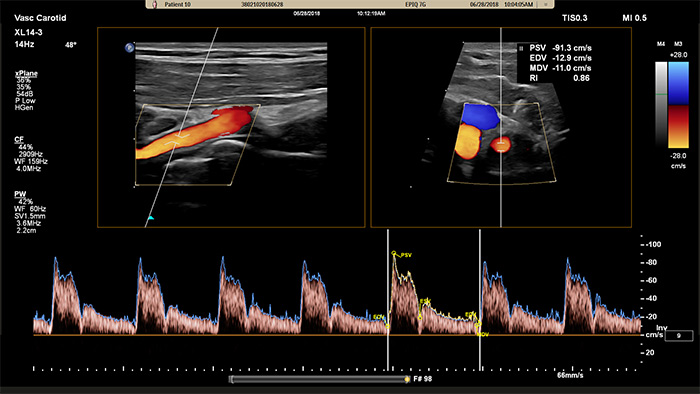

La sonde xMATRIX XL14-3 offre une imagerie xPlan qui va au-delà de l’approche conventionnelle des examens vasculaires, en fournissant des images en temps réel, simultanément dans des plans longitudinaux et transversaux. Atout majeur : avec l’imagerie xPlan, il n’est plus nécessaire de faire pivoter la sonde pour obtenir des vues orthogonales. Un simple mouvement de la boule de commande permet d’obtenir une évaluation anatomique complète, ce qui permet de gagner du temps lors de l’examen.

La sonde xMATRIX XL14-3 offre également les capacités du Doppler xPlan. Le Doppler pulsé xPlan permet un positionnement précis du volume d’échantillonnage du Doppler en utilisant des images de référence longitudinales et transversales. Atout majeur : Doppler xPlan réduit les erreurs de positionnement du volume d’échantillonnage. Il offre aussi une reproductibilité plus fiable et une meilleure cohérence lors de l’échantillonnage d’une sténose importante.